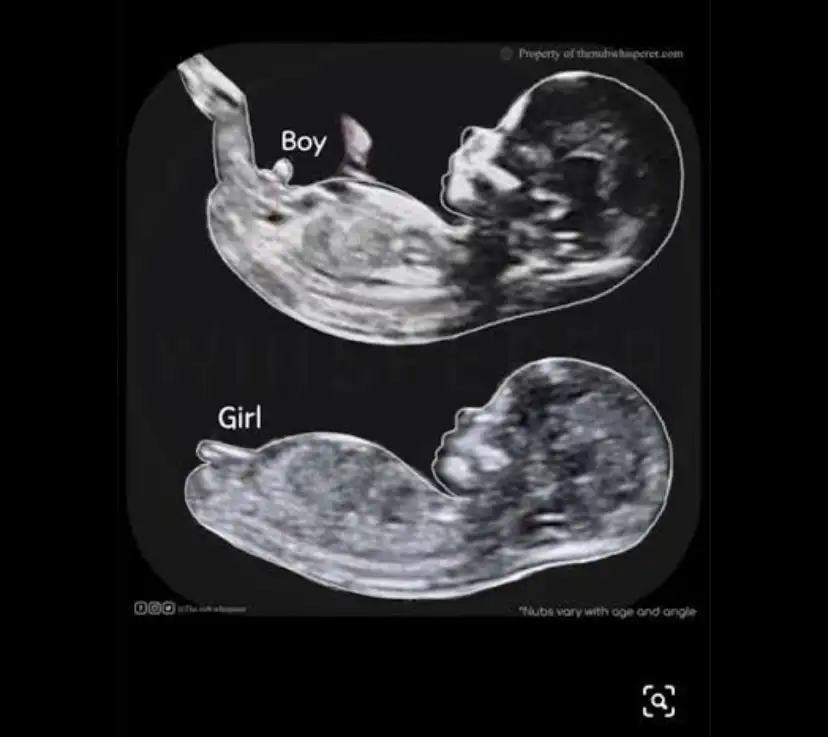

Nuba göre erkek oluyor sanırımAy kızlar ben nub filan hiç bilmiyodum banada bi bakın kız mı erkek mi nuba göre![]()

Nub u nasıl anlıyorsun net bir şekilde, bende intten cok baktim ama anlamıyorum, benimkinin burda nub belli mii B BarbieveKenKesin kız

Bana hepsinin aynı gelmesinerden anlıyorsunuz

bence erkek ..benim de ultrasonda boyle görünüyodu irice.tahminimce erkektirNub u nasıl anlıyorsun net bir şekilde, bende intten cok baktim ama anlamıyorum, benimkinin burda nub belli mii B BarbieveKen